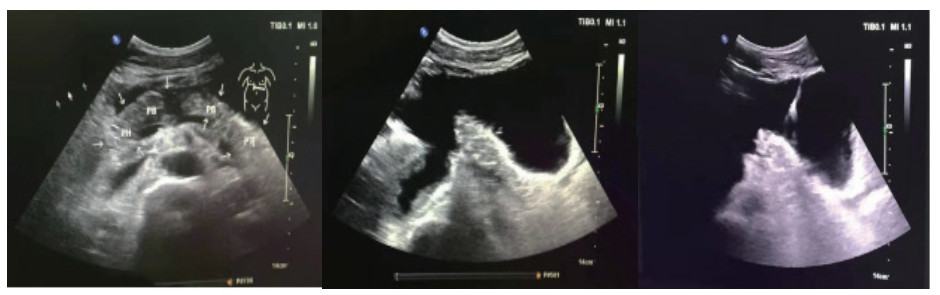

患者男,26岁,维吾尔族,以“高处坠落致腹部疼痛2 d”为主诉入院。患者于2019-03-26凌晨1时左右饮酒后不慎从2 M高处楼梯上摔下,伤及头部、腹部及腰背部,左侧面颊部见少量出血,当时神志状态不明,是否存在腹部及腰背部疼痛,无人知晓。至清晨8时左右,被家属发现俯卧于楼梯口,患者昏睡,周围未见呕吐物,楼梯上可见少量血迹,面颊部擦伤已结痂,呼唤能醒,自诉腹部及腰背部疼痛不适,无头痛、头晕,无恶心、呕吐,遂被立即送往当地县人民医院,CT检查后考虑“胰腺断裂”,给予输液治疗(具体不详),患者意识逐渐转清,可简单对答。为进一步治疗,于2019-03-26晚21:45转入阿克苏农一师医院。入院查体:体温37.1℃,呼吸20次/min,心率90次/min血压120/79 mmHg,腹部平坦,腹皮肤表面未见明显挫伤痕迹,未见胃型,未见肠型,未见蠕动波,无腹壁静脉曲张,未见手术瘢痕,全腹压痛,腹肌紧张,上腹部明显,反跳痛全腹存在,未触及液波震颤,未及腹部包块,肠鸣音减弱,1~2次/min。双肾区有叩痛,右侧明显。骨盆挤压试验(-)。急诊检查生命体征尚稳定,拟诊“腹部闭合性损伤:胰腺断裂?右肾动脉损伤、右肾坏死?”收入ICU。入院诊断:闭合性腹部损伤,胰腺断裂Ⅳ级(主胰管断裂)、弥漫性腹膜炎、右肾动脉损伤、右肾梗死。入院实验室检查:WBC:11.5×109/ L, N:92.1%, Hb 10.5 g,PCT:4.32 ng/mL。入院影像学检查:胸部+腹部增强CT(2019年3月2号晚21:45):右肺下叶炎症,右侧胸腔少量积液,双侧局部胸膜肥厚,胰腺断裂伴周围低密度病灶,考虑假性囊肿形成,右肾动脉损伤,右肾无灌注,腹腔、盆腔积液(考虑血性),腹腔内局部脂肪间隙浑浊,考虑腹膜炎,提示:腹腔内部分肠管明显扩张并积气。此报告为危急值报告!治疗经过:入住ICU,先期放置胃管行胃肠减压,4 d后起经鼻空肠营养,逐渐加量至全量;主要药物泮托拉唑抑酸护胃,生长抑素抑制胰酶分泌,头孢他定+甲硝唑抗感染;本案例入院时创伤发生已过24 h,右肾不显影提示肾动脉梗死造成右肾梗死,介入再通已过时间窗,故放弃介入,不做进一步处理;入院当天腹部增强CT提示胰腺断裂Ⅳ级,胰管完全离断,胰头与胰体尾明显分离,腹腔积液以左中上腹、左下腹居多,腹膜刺激征遍及全腹,按传统观点手术指征明确。但血流动力学稳定,读CT片并完成MRCP后,排除空腔脏器破裂,明确积液集中于上腹部和左下腹,大胆尝试在创伤ICU支持下行非手术治疗。2019-03-29患者行B超检查,示腹腔积液,积液相对集中于左中上腹和左下腹(图 1)。B超定位引导下行左上腹和左下腹穿刺引流(图 2),引出液体性状淡血性,引流效果明显,患者病情较前好转,但血象仍较高,予头孢他啶和甲硝唑抗感染。入院4 d后腹胀缓解即行经鼻空肠营养,以后视腹胀情况逐日加量,5 d后出ICU,因经济问题普通病房住院10 d,带管出院。出院1个月后来院行ERCP术置管困难,放弃置管内引流,继续腹腔引流管回家,未做任何处理。3个月后腹腔引流管自行脱落,6个月后来院复查CT(图 3),胰腺外形基本恢复正常,腹腔无积液,饮食正常,自诉家中腹腔引流管脱落后无任何不适。

| 图 3 患者随访复查CT对比 |